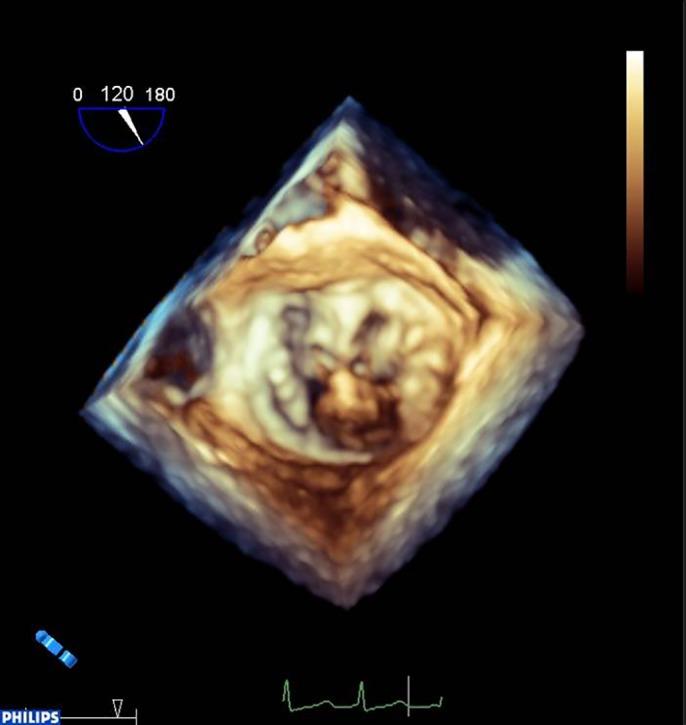

Quantitative analysis is an important part of the morphological assessment of the diseased mitral valve. It can be used to describe valve anatomy, pathology, function and the mechanisms of disease. Echocardiography is the main source of indirect quantitative data that is comparable with direct anatomic or surgical measurements. Furthermore, it can relate morphology with function. This review provides an account of current mitral valve quantification techniques and clinical applications.